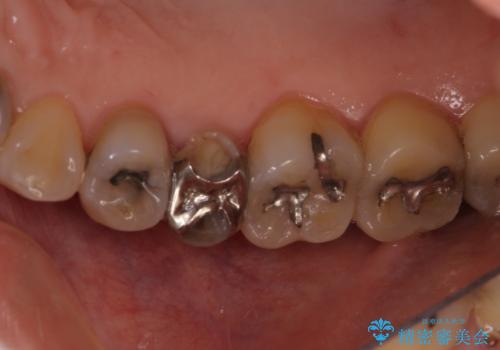

- 前歯のすきっぱを主訴にご来院された患者様です。他院でつめものやラミネートべニア(前歯の表面のみセラミックを貼り付ける)を行っていましたが、頻繁に外れることに悩まれており、クラウン(歯全体をセラミックがつつむ)をご希望されました。また、奥歯に大きな虫歯があり、歯が割れていたため、奥歯の治療も併せて行いました。

咬み合わせや元のご自身の歯の色に特徴があったため、セラミッククラウンを修正したり、隣の歯を金属を外して白いつめものに変えたりして経過観察を長めに行いました。

右上の歯に関しても、大きな虫歯があったため、前歯の経過観察の間に治療を行いました。